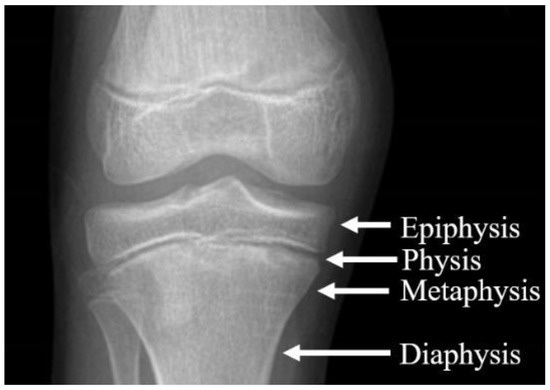

The growth plate, also termed the physis, is a cartilaginous area of the bone that is responsible for longitudinal growth. The epiphysis is the very proximal or distal part of the bone, which articulates with the epiphysis of another bone to form a joint. An apophysis is an epiphysis that does not articulate with another bone. The diaphysis of a bone is the mid-section part of the long bone. The metaphysis is the part of the diaphysis that is adjacent to the physis. This part of the bone is active with cell division and growth. Finally, the periosteum is the membrane that lines the outer surface of all bones except at the joint. (See Figure 1.)

Figure 1. Physeal Growth Plate |

Source: Frydrýšek K, Čepica D, Halo T, et al. Biomechanical analysis of staples for epiphysiodesis. Applied Sciences. 2022;12(2):614. |